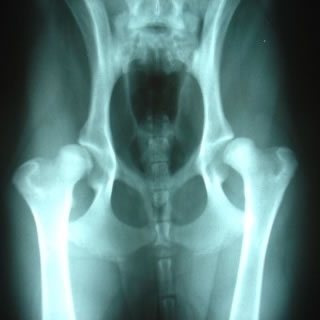

Displasia Coxofemoral

Doença hereditaria altamente incapacitante que tem tratamentos eficazes quando diagnosticada cedo.